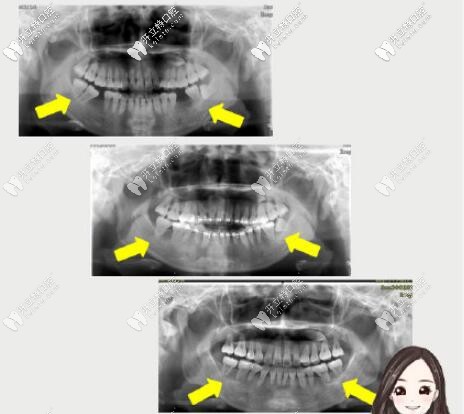

這位顧客主訴沒下巴。骨性+牙性齙牙、下頜后縮,磨牙缺失咬合已經(jīng)錯位。

這時原本“廢棄”的智齒派上用場,第三磨牙前移轉(zhuǎn)正為第二磨牙,參與到咬合關(guān)系當(dāng)中。

拔牙矯正,智齒替磨牙,調(diào)整頜平面,終收獲了現(xiàn)在的面型